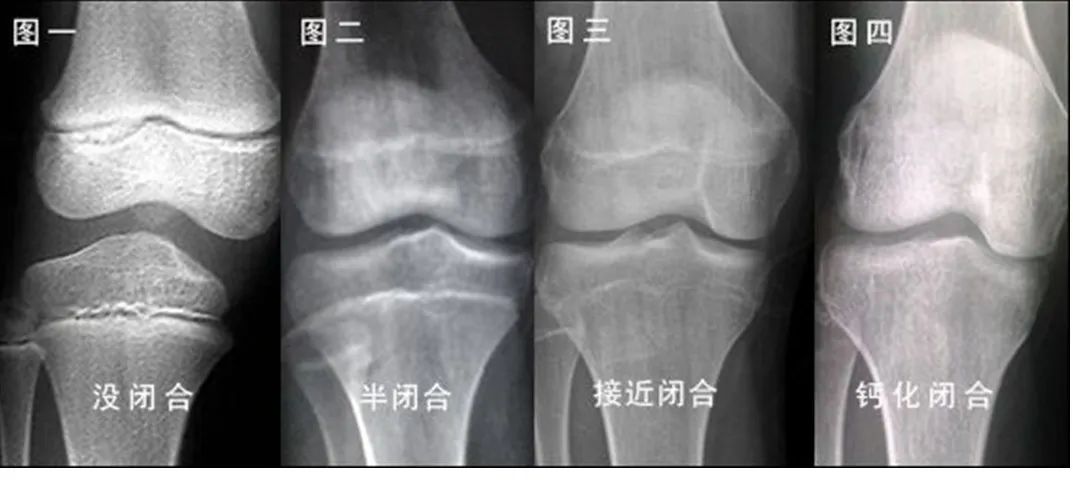

骨龄检查不但可以排查“早长“现象及导致孩子晚长的相关疾病,通过及时干预将对身高的不良影响降到最低,还可以通过对骨龄发育速度的合理调控来为孩子争取更多长高时间,助力孩子实现理想身高!3岁以上孩子建议定期检测骨龄,及时了解【长高潜能】。

虽然肥胖的孩子短期内比同龄人高一些,但其内分泌水平可加速骨骺的快速闭合,影响最终成年身高。所以肥胖孩子的骨龄超前较多见。

身高管理的一项重要内容是提醒家长要关注和预防肥胖。营养过剩会导致骨龄加速发育,而忽视骨龄就会影响到终身高。身高管理门诊的当务之急是从营养角度控制儿童体重,调控骨龄发育速度,避免骨龄过早“发育”。最好的状态是,骨龄始终等于或低于生活年龄。

长高是一场倒计时,一旦生长板闭合

长高的机会就很小了